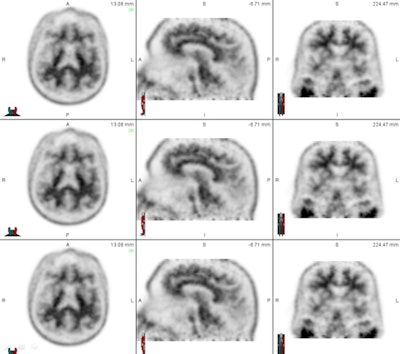

Dr. Ameya Nayate, a neuroradiology fellow in the department of radiology and nuclear medicine and lead author of the current study, noted that beta amyloid binds to brain regions such as the frontal lobe, temporal lobe, parietal lobe, and cingulate gyrus. These areas are associated with memory and other cognitive functions.

"With that specific information, we can look at those areas to determine if there is significant beta-amyloid deposition," Nayate said when he presented study results at the 2013 RSNA annual meeting. "However, in order to do that, we need to compare [those brain regions] to an internal standard: an area of the brain that does not have significant beta-amyloid deposition."

One such region is the cerebellum: Prior research has found no significant beta-amyloid deposition in this area, regardless of whether subjects are healthy or have Alzheimer's. SUV could potentially be measured in these regions and compared with SUV in the six brain regions susceptible to beta-amyloid deposits, producing an SUV ratio that indicates whether a patient has a higher burden of amyloid plaque. Physicians could use this information along with clinical findings to estimate a patient's risk of developing Alzheimer's disease.